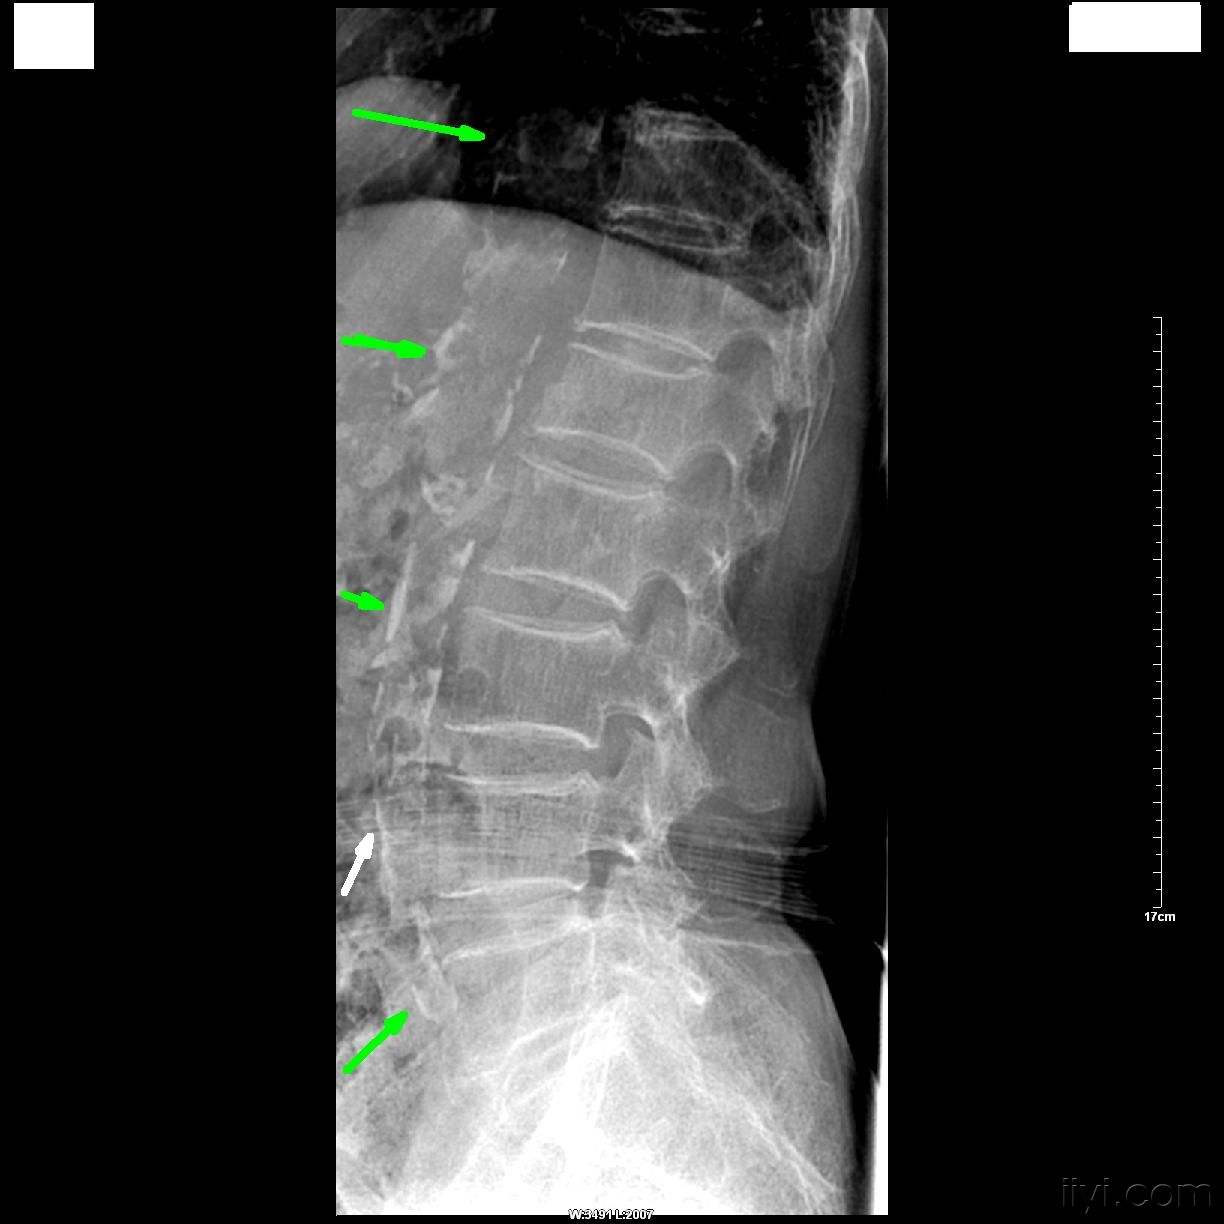

结果看什么?看那些威胁健康的“白色阴影”(图中标示箭头部位均为钙化部位)

侧位腹部X线:当血管壁钙化时,可通过X光片看到明显的血管轮廓,图中所示为典型腹主动脉钙化。